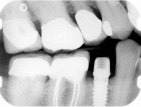

Radiographically, a dental implant looks like this:

Implant in bone Implant with crown attached